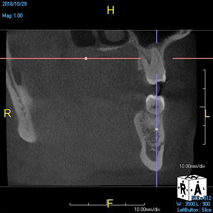

(11.) A pathosis apical to the maxillary central incisors was initially not diagnosed after evaluating the periapical film; however, the CBCT image revealed its presence. Only using the CBCT image could it be determined that the lesion was not odontogenic in origin and that it did not involve the nasopalatine foramen. This diagnosis was supported by a referral to an oral and maxillofacial radiologist.

Figure 11

(12.) A pathosis apical to the maxillary central incisors was initially not diagnosed after evaluating the periapical film; however, the CBCT image revealed its presence. Only using the CBCT image could it be determined that the lesion was not odontogenic in origin and that it did not involve the nasopalatine foramen. This diagnosis was supported by a referral to an oral and maxillofacial radiologist.

Figure 12